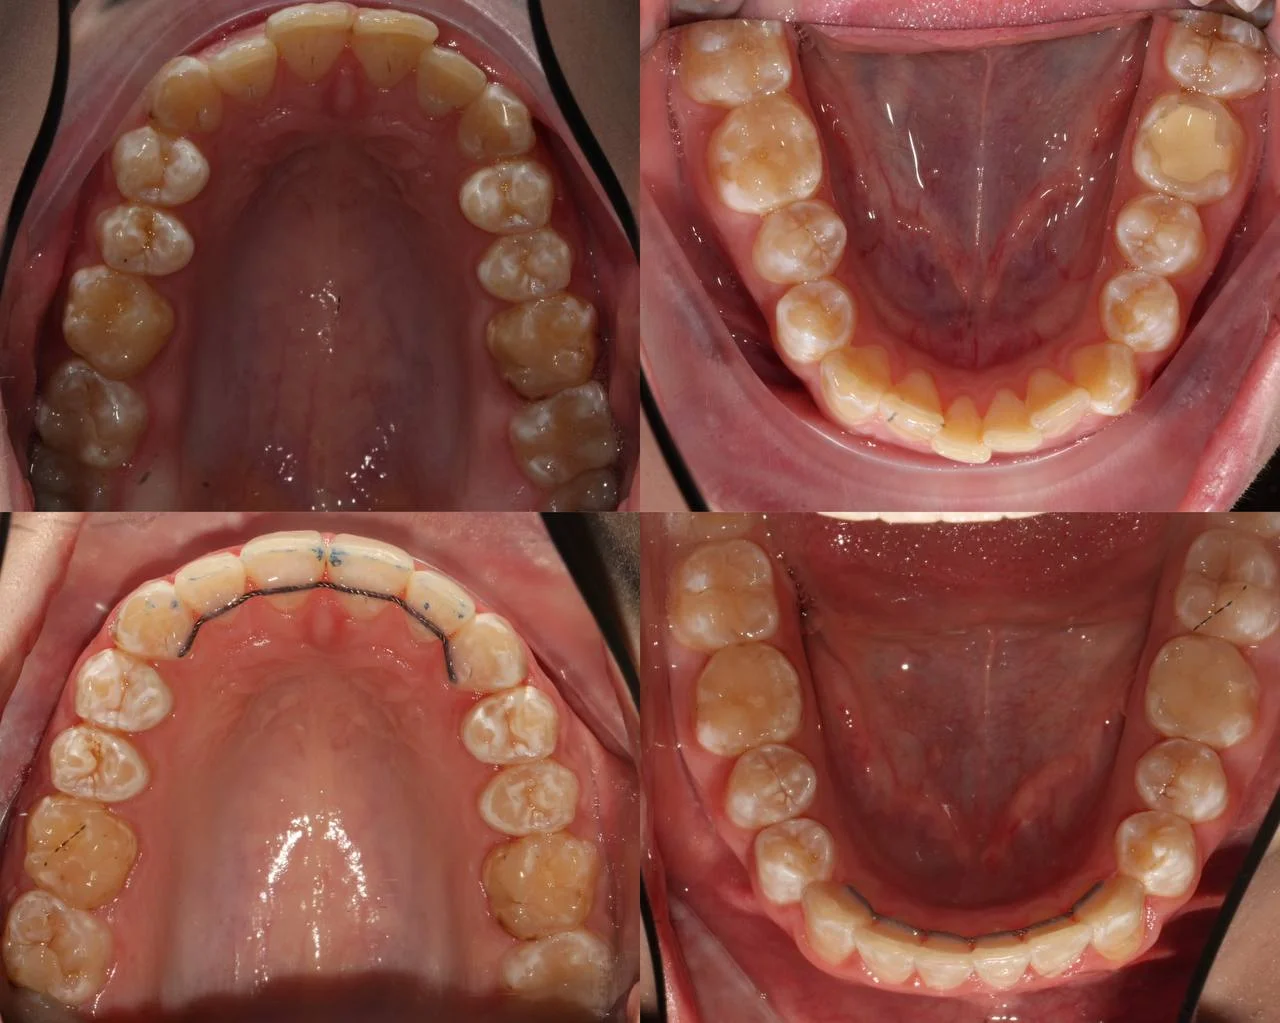

Нарушение соотношения челюстей и неправильное положение зубов — зубные ряды смыкались некорректно, зубы стояли со смещением.

Прозрачные элайнеры Click на обе челюсти. Выровнять зубы и нормализовать смыкание. Основной набор — 20 кап. Срок — около 1 года.

Проблема: Пациентку не устраивало положение зубов и то, как смыкаются челюсти. Зубы стояли неровно, ряды сходились неправильно.